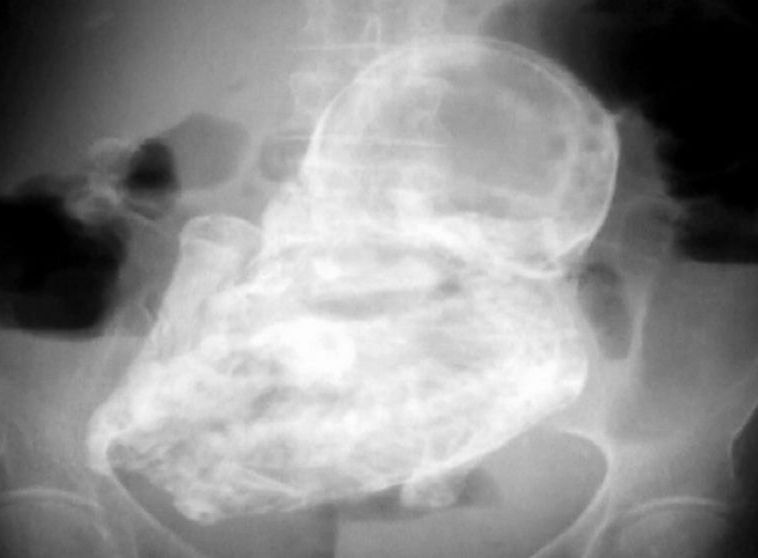

“When you get old cartilage in the knee, it calcifies,” Garcsi explains. The calcification of the tissue protects the mother from infection, but also means the “stone” baby can remain in the abdomen undetected for decades.

“Most of the time people find these and [sometimes] even after they’re found and don’t do anything about it because they’re totally asymptomatic,” said Garcsi.

The rate of an abdominal pregnancy is about 1 in 10,000 pregnancies; however, Garcsi said modern medical care usually identifies any issues that would lead to a lithopedion before the “stone” baby can form.